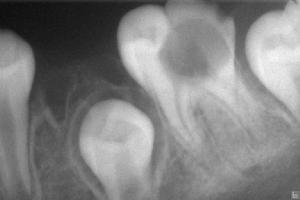

X線片檢查有利於發現隱蔽部位的齲損,還可採用螢光顯示法、顯微放射攝影方法或氬離子雷射照射法幫助診斷。